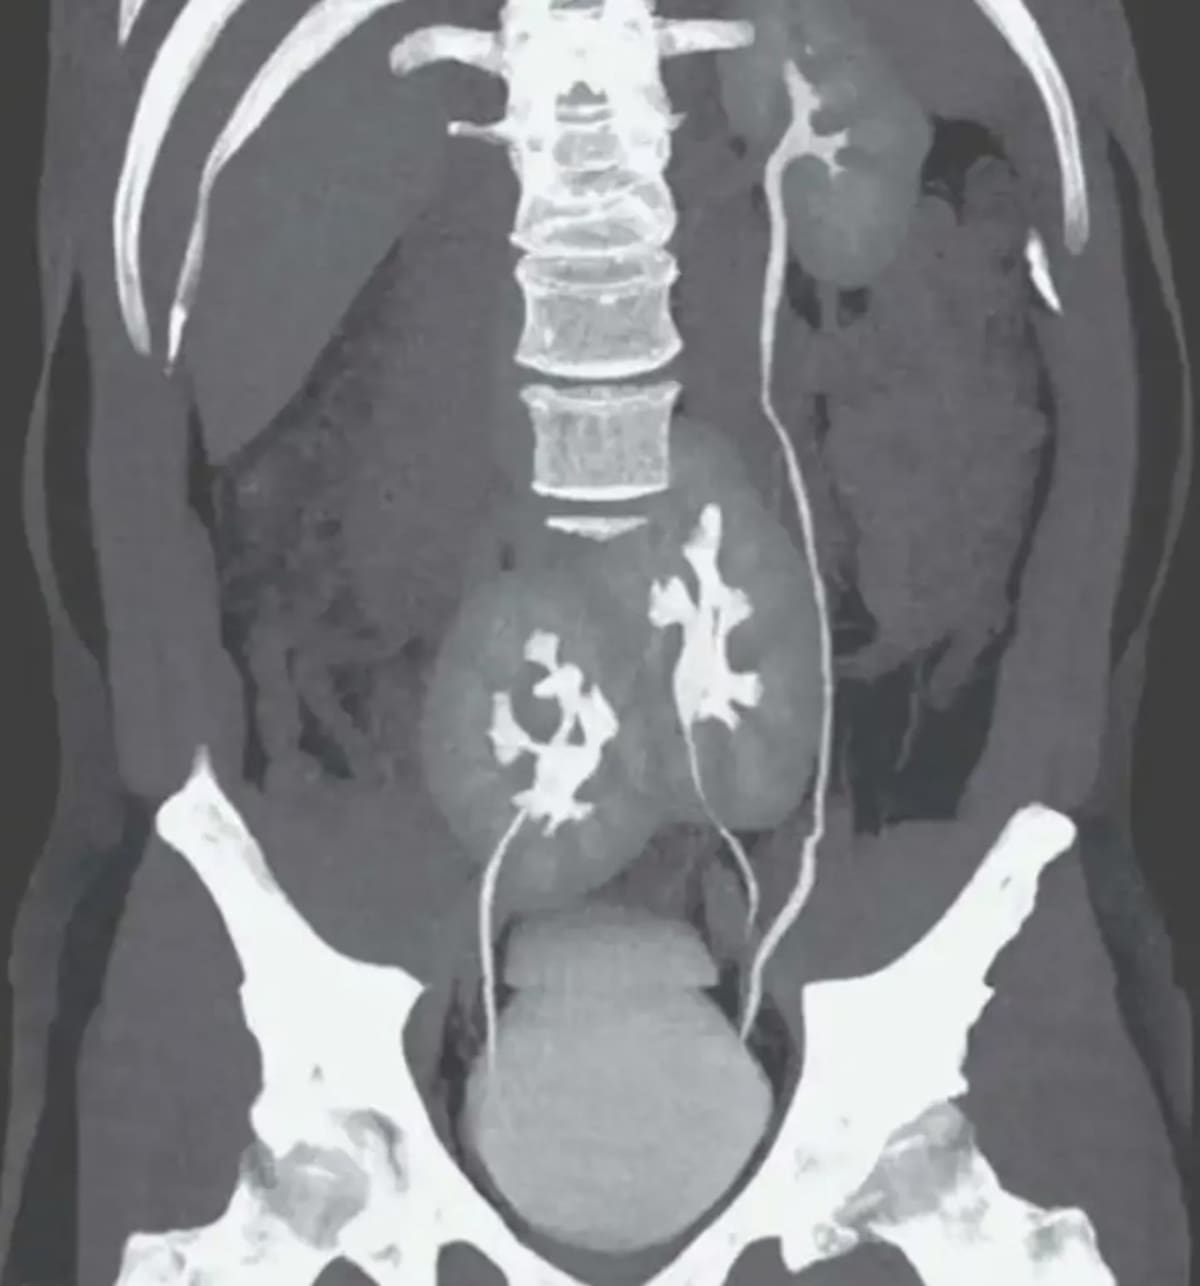

La imagen obtenida a través del estudio reveló que el paciente poseía tres riñones en lugar de dos. Aunque en el lado izquierdo tenía un solo riñón como sucede normalmente, en la derecha podían verse dos que se encontraban fusionados.

La tomografía donde se vieron los tres riñones. Foto: New England Journal of Medicine.